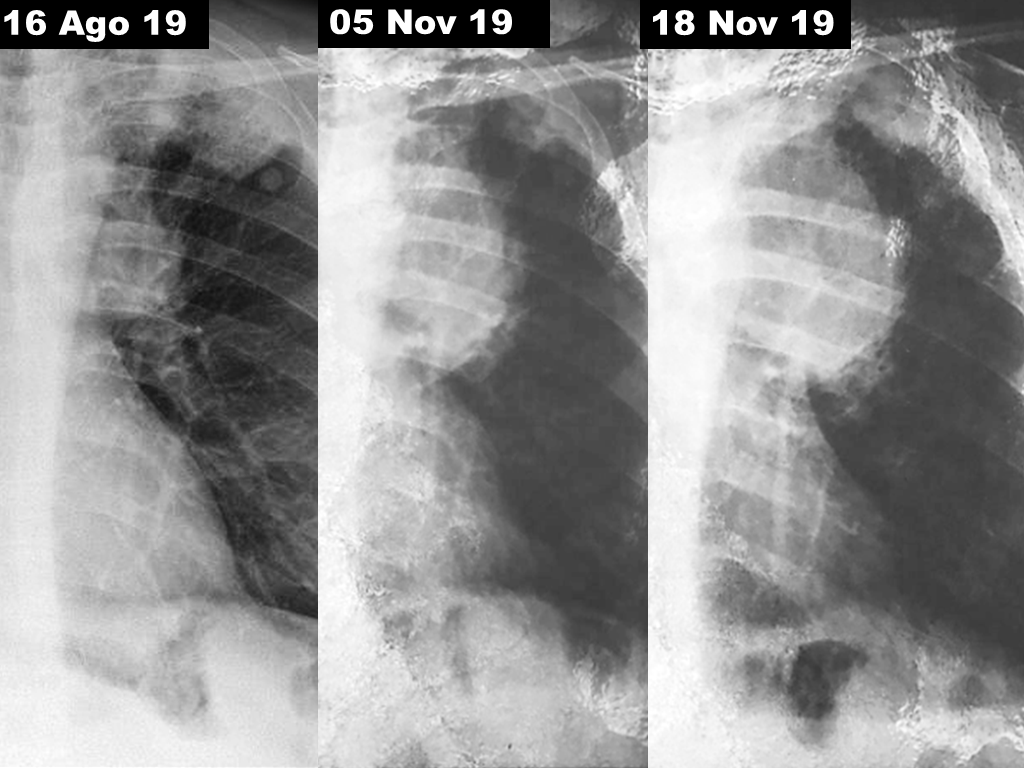

O carcinoma de pulmão de células pequenas é um tumor com localização central preferencial (90% dos casos) e tem direta relação etiopatogênica com o tabagismo. Há quem diga que esse subtipo histológico é dificilmente diagnosticado em não fumantes. De todos os cânceres de pulmão é o que oferece pior prognóstico. Seu tempo de duplicação celular gira em torno de 30 dias e, por isso, apresenta rápido crescimento temporal como ilustrado na figura acima. Disseminação precoce a distância é observada com muita frequência (60-70% dos casos). Embora mais agressivo, de todas as neoplasias pulmonares é o tipo histológico que melhor responde tanto à quimioterapia quanto à radioterapia.

Homem branco, 62 anos, tabagista pesado (88 maços/ano) vem em acompanhamento clínico periódico devido ao achado incidental de nódulo pulmonar em segmento apical do lobo inferior esquerdo. RX de tórax em agosto/2019 identifica mudança no padrão radiológico habitual. Solicitada tomografia computorizada que confirma lesão expansiva com 11 cm no seu maior diâmetro em lobo superior esquerdo, em íntimo contato com o arco aórtico. Extenso comprometimento linfonodal em mediastino ipsilateral. Pleura relojes replica españa mediastinal comprometida e pequeno derrame pleural. Múltiplas metástases ósseas e em adrenal direita. Broncofibroscopia visualiza e biopsia uma lesão infiltrativa em parede posterolateral do brônquio principal esquerdo, que se estende à divisão superior do brônquio do lobo superior e reduz o seu calibre. O exame anatomopatológico da peça descreve um carcinoma neuroendócrino de células pequenas primário de pulmão.